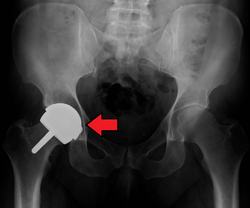

![]() An X-ray showing a left hip (right of image) that has been replaced, with the ball of this ball-and-socket joint replaced by a metal head that is set in the femur and the socket replaced by a cup | |

Hip replacement is a surgical procedure in which the hip joint is replaced by a prosthetic implant, that is, a hip prosthesis. Hip replacement surgery can be performed as a total replacement or a hemi (half) replacement. Such joint replacement orthopaedic surgery is generally conducted to relieve arthritis pain or in some hip fractures. A total hip replacement (total hip arthroplasty or THA) consists of replacing both the acetabulum and the femoral head while hemiarthroplasty generally only replaces the femoral head. Hip replacement is one of the most common orthopaedic operations, though patient satisfaction varies widely. Approximately 58% of total hip replacements are estimated to last 25 years.[1] The average cost of a total hip replacement in 2012 was $40,364 in the United States, and about $7,700 to $12,000 in most European countries.[2]